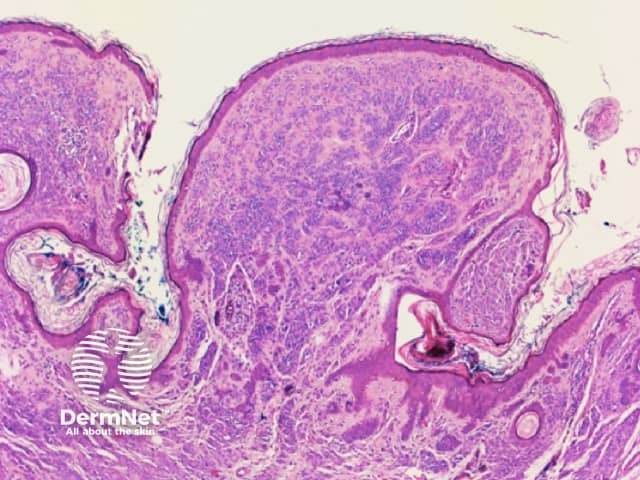

Clods are solid rounded structures of sufficient size to show an appreciable variability in size. Their colour depends on the nature and, in the case of melanin, depth of the substance they comprise (Figures 37-50). Other terms have been used for clods in specific settings such as blue-grey ovoid nests for grey and / or blue clods seen in basal cell carcinoma.

Figure 37a Figure 37b

Figure 38 Figure 39 Figure 40 Figure 41

Figure 42 Figure 43 Figure 44

Figure 45a Figure 45b Figure 46a Figure 46b

Figure 47

Figure 48

Figure 48. Diagram. Brown, grey and blue clods are due to nests of melanin-containing cells at different levels in the skin. From Kittler et al (1).

Figure 49a Figure 49b Figure 49c Figure 49d

Figure 50a Figure 50b